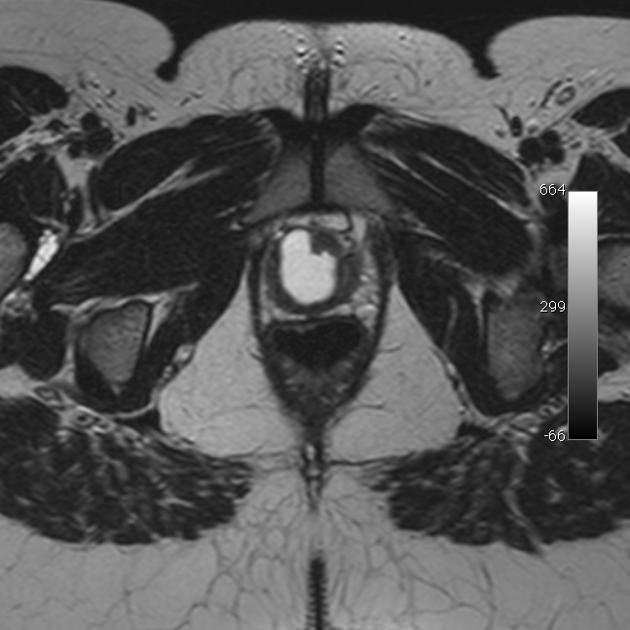

Diagnosis?

MRI appearance?

Uterine leiomyoma.

MRI: T1 isointense to myometrium, T2 hypointense. (May be hyperintense on T1/2 if undergoing fatty degeneration) Signal dropout if calcifications.